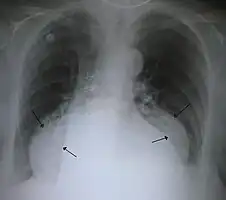

-

A large hiatal hernia on chest X-ray marked by open arrows in contrast to the heart borders marked by closed arrows